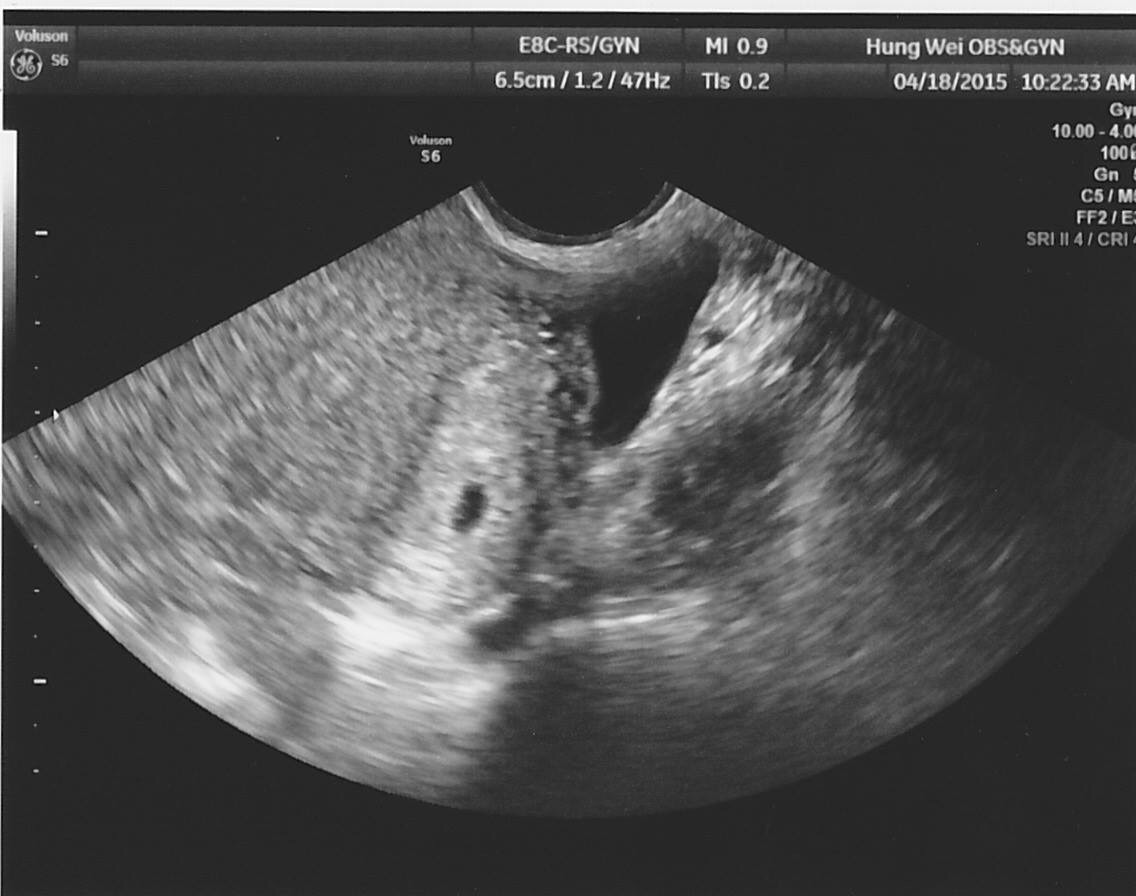

橢圓形的胎囊

(用掃描的有點不清處)

星期六照到的胚囊 忘記問醫生幾mm了

醫生說不到5週

醫生也沒有說他不健康

上1次月經是3/15-3/21

今天看了看 總覺得有2個小白點

請問那個是什麼?還是超音波照片照起來都會這樣?

(胚囊裡面有2個小白點)

Ps:有點橢圓形像豆狀是正常的嗎